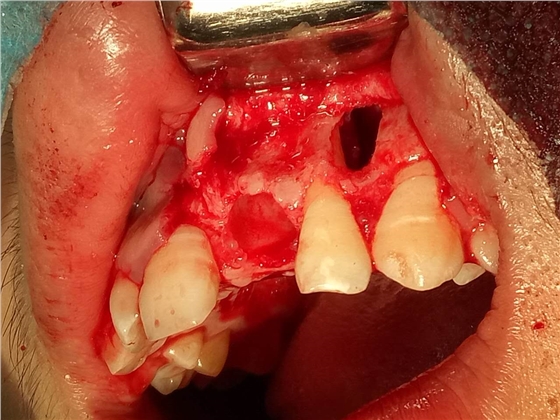

死髓牙2度,沒(méi)保留價(jià)值了,外傷造成的外吸收,即使到充也容易出問(wèn)題。和患者溝通,要求做種植,用了兩個(gè)骨膠原,側(cè)切、尖牙沒(méi)事,側(cè)切做了一次根充